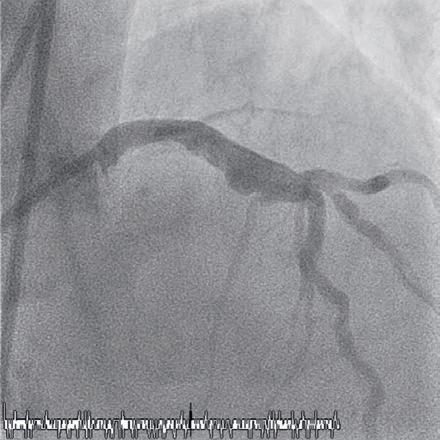

Intracoronary imaging

Among the major changes to the latest version of the guidelines is a new emphasis intravascular imaging. When performing revascularisation via PCI, intracoronary imaging—in the form of intravascular ultrasound (IVUS) or optical coherence tomography (OCT) —is deemed as being helpful to guide interventions and enhance results, especially in complex scenarios including left main disease, bifurcations, or long lesions.

on a multitude of randomised controlled trials showing consistent substantial clinical benefit,” said Lorenz Räber (Bern University Hospital, Bern, Switzerland), highlighting the importance of this new recommendation to Cardiovascular News. “Europe is lagging behind, as many believe angio is enough, so the upgrade is expected to fuel the use of imaging for complex lesions. Currently, there is no other technical refinement of PCI that reportedly improves clinical outcomes to the degree observed with intracoronary imaging.”

“Meta-analysis of randomised clinical trials had already shown that intracoronary image guidance of PCI improves patient outcomes and saves lives,” said Javier Escaned (Hospital Clinico San Carlos, Madrid, Spain). “But the IA recommendation for IVUS in the updated ESC guidelines is crucial, as it reflects expert consensus based on a definite body of evidence supporting the positive impact of IVUS, specifically for patients with anatomically complex lesions treated with PCI.”